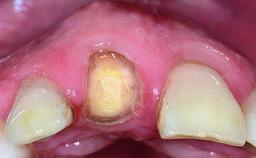

Replacement of a Failing Upper Left Central Incisor: Immediate Placement of an RC Bone Level Implant and Provisionalization

A healthy 23-year-old female patient was referred for a consultation on replacing tooth 21 with an implant-supported restoration. The patient had recently moved to the area and reported a history of endodontic and periodontal treatment for tooth 21. The tooth had been deemed non-restorable by her previous periodontist but since she was going to be moving, he recommended consulting to a dentist in her new city to continue her treatment. A review of her medical history yielded no significant findings and no known drug allergies. The analysis of her smile revealed a medium to high symmetrical smile line and a slightly discolored tooth 21.

Shape of Tooth Crowns Rectangular Triangular

Soft Tissue Anatomy Intact Defective